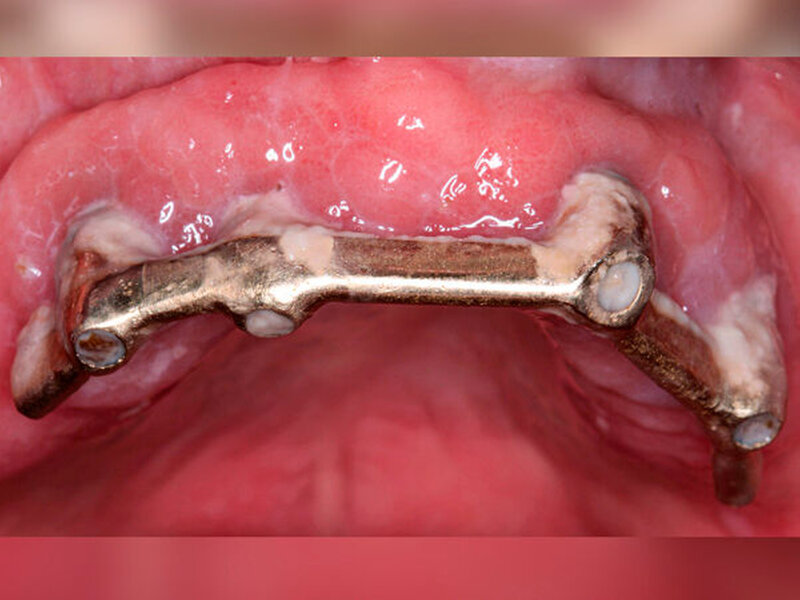

Wird der Biofilm um Implantate nicht entfernt (Abbildung 1), so kann die Entstehung einer periimplantären Mukositis oder Periimplantitis die Folge sein. Während die periimplantäre Mukositis eine reversible Entzündung des suprakrestalen Weichgewebes darstellt, ist bei der Periimplantitis zusätzlich der das Implantat umgebende Knochen betroffen [Lindhe/Meyle, 2008]. Letztere ist nur bedingt reversibel und geht mit erhöhten Taschentiefen, Knochenverlust, gegebenenfalls Pusbildung sowie im Endstadium mit Implantatlockerung und Implantatverlust einher. Mehr als 50 Prozent der Zahnimplantate sind von einer periimplantären Mukositis betroffen [Heitz-Mayfield/Salvi, 2018]; jedes zehnte Implantat und jeder fünfte Patient mit Implantaten entwickeln nach einer Tragedauer von fünf bis zehn Jahren eine Periimplantitis [Mombelli et al., 2012]. Es ist anzunehmen, dass die periimplantäre Mukositis eine Vorstufe der Periimplantitis darstellt und unbehandelt zur Ausprägung eben dieser führt. Studien haben gezeigt, dass der Übergang von einer periimplantären Mukositis zur initialen Periimplantitis fließend ist und weder klinisch, radiologisch, mikrobiologisch noch immunologisch eindeutig diagnostiziert werden kann [Klinge/Meyle, 2012]. Eine weitere Untersuchung ergab, dass die Behandlung der Mukositis nach zwölf Wochen lediglich bei 70 Prozent der Patienten zur vollständigen Ausheilung führte [Bunk et al., 2020]. Erschwerend kommt hinzu, dass periimplantäre Erkrankungen im Vergleich zu parodontalen Erkrankungen eine höhere Progredienz aufweisen und sich die Therapie nicht einfach darstellt.